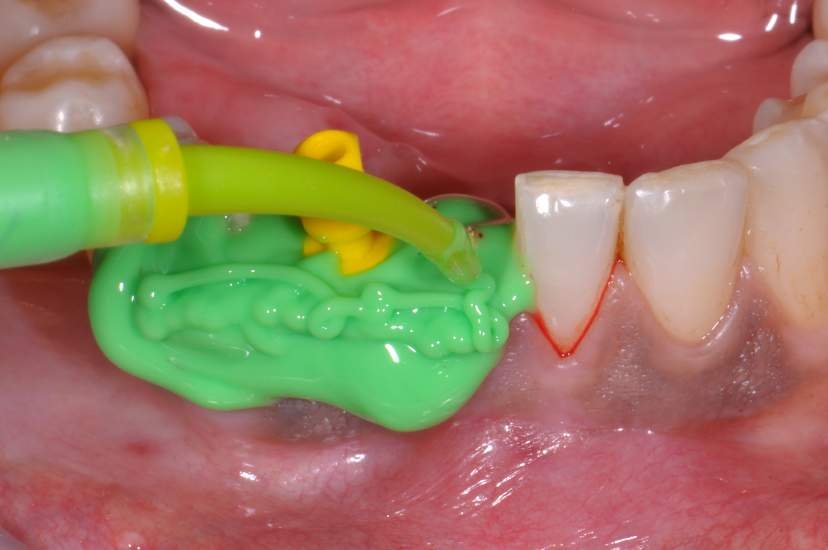

Os implantes Slim Pilar, apresentam alta versatilidade protética possibilitando aplicação de coroas Cimentadas ou Parafusadas (Fig. 3). O Sistema protético é simplificado, utilizando o mesmo sistema aplicado em implantes Implacil Cone Morse para transferentes, coifas e análogos. E a aplicação é tanto para elementos Unitários como para Múltiplos.

O procedimento cirúrgico para os implantes Slim segue um protocolo semelhante como outros implantes, porém muito simplificado. Normalmente utilizase a técnica anestésica infiltrativa. Um retalho mucoperiosteal deve ser rebatido para uma observação direta do rebordo ósseo disponível. No entanto, quando o tecido queratinizado e o volume ósseo abundantes estiverem presentes, uma cirurgia flapless é muitas vezes o protocolo cirúrgico de escolha.2

CASO CLÍNICO

Paciente com perda do incisivo central inferior do lado direito, utilizando uma prótese fixa em zircônia com estética e adaptação deficientes.